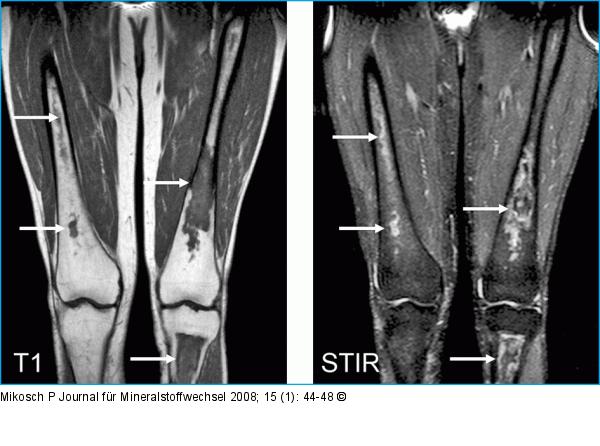

Abbildung 1: Knocheninfarkt MRI T1 und STIR untere Extremitäten: Knocheninfarkte in den Femura beiderseits und in der linken Tibia (Pfeile). |

MRI T1 und STIR untere Extremitäten: Knocheninfarkte in den Femura beiderseits und in der linken Tibia (Pfeile). |